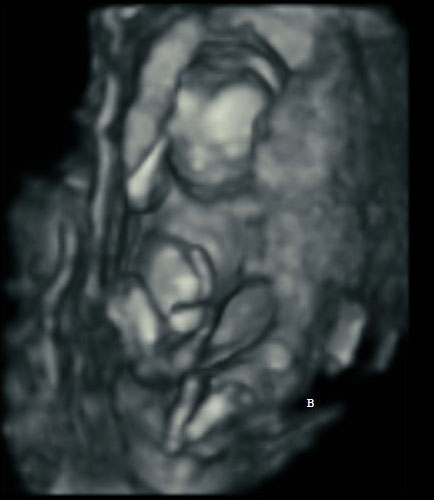

Here’s how ultrasound works in pregnancy: As early as 16 weeks, women can see a “fetal portrait” of their baby and determine its gender. Ultrasound technology has improved dramatically over the decades from flat, grainy black and white images to the current three-dimensional time experience.

Most hospitals offer some 3D scanning, but 3D ultrasound produces images that show the width, height and depth of a developing child. Rather than sending sound waves straight into the womb and recording when they bounce back as is common in 2D imaging, 3D ultrasound sends sound waves from different angles. A computer then renders a 3D image based on this data.

4D ultrasound adds movement as it occurs. The fourth dimension is time. You’re actually watching your baby live in 3D mode. How cool is that?